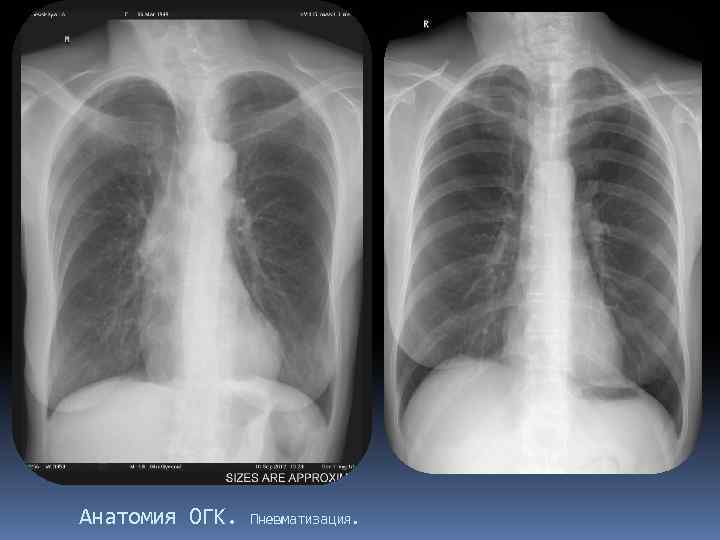

Анатомия ОГК. Пневматизация.